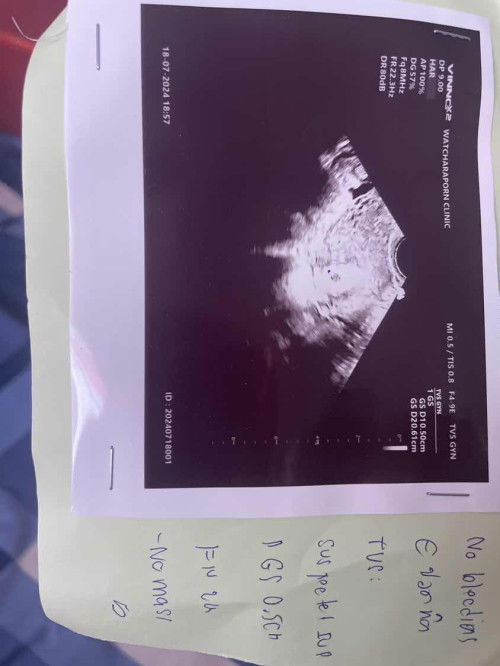

ช่วยดูอัลตร้าซาวด์ หน่อยคะ หมอบอกว่าตั้งครรภ์ น่าจะ 4 week ตรวจวันที่ 18 กค67 หมอนัดอีกที 1 สค67 ค่ะ เพื่อดูพัฒนาการ ได้ยา วิตามินบีรวม และโฟลิค มาทานค่ะ มีภาวะpcos ท้องแรก แบบไม่ได้เตรียมการบำรุงอะไรมาก่อนค่ะ กังวลเรื่องความเสี่ยงต่าง ๆ มีอะไรบ้างคะ และช่วงนี้ควรบำรุงอะไรบ้าง ทานอาหารบำรุง ประเภทไหนคะ และกังวลว่านัดอัลตร้าซาวด์ 1 สค 67นี้ กลัวไม่เจอไข่แดงและตัวอ่อน #ขอความคิดเห็นของคุณแม่หน่อยค่ะ

Pcos ค่ะไม่ได้บำรุง อะไร เลยมาแบบธรรมชาติค่ะ เห็นคลิปในติ้กต้อก มีอาการpcos เจอถุงตั้งครรภ์ เจอไข่แดง แต่ไม่เจอตัวอ่อน จะweek ที่ 12 ไข่แดงในถุงตั้งครรภ์ค่อยๆฝ่อ และต้องขูดเอาถุงตั้งครรภ์ออก และให้นว่าไม่มีอาการอะไรเลย มีเพียงไปตรวจตามรอบคุณหมอนัด 📍ส่วนเรื่องของเราคือ ไปหาหมอ หมอบอกว่า ท้องอ่อนๆพึ่งปฏิสนธิ ซาวด์ทางช่องคลอด เจอถุงตั้งครรภ์ และนัด อีก 2 week คือ 1 สค67 นี้เพื่อดูพัฒนาการ ค่ะ /// มีความกังวลค่ะ ภาวะpcos นี้ มีโอกาสมากน้อยเเค่ไหนคะ กี่เปอร์เซ็นคะ อยู่จนคลอด ขอบคุณค่ะที่ให้ความอห็น #ขอความคิดเห็นของคุณแม่หน่อยค่ะ